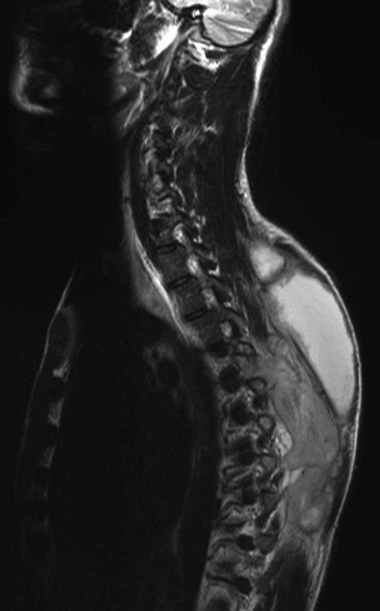

Blood tests showed a normal white cell count and differential, a C-reactive protein level of 180 mg/L (reference range, 0–4 mg/L), and an erythrocyte sedimentation rate of 64 mm/h (reference range, 0–15 mm/h). HIV serology was negative. Magnetic resonance imaging of the thoracic cord showed large, bilateral collections within the rectus spinae muscles extending between T3 and T10, and destruction of the spinous process of T5. There was also high signal in the facet joints at this level, suggesting an infection arising from them (C).